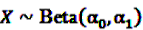

and  be random variables to describe the occurrence of drug exposure i and ADR j, respectively. The a priori expectations of X and Y are obtained as:

be random variables to describe the occurrence of drug exposure i and ADR j, respectively. The a priori expectations of X and Y are obtained as: and